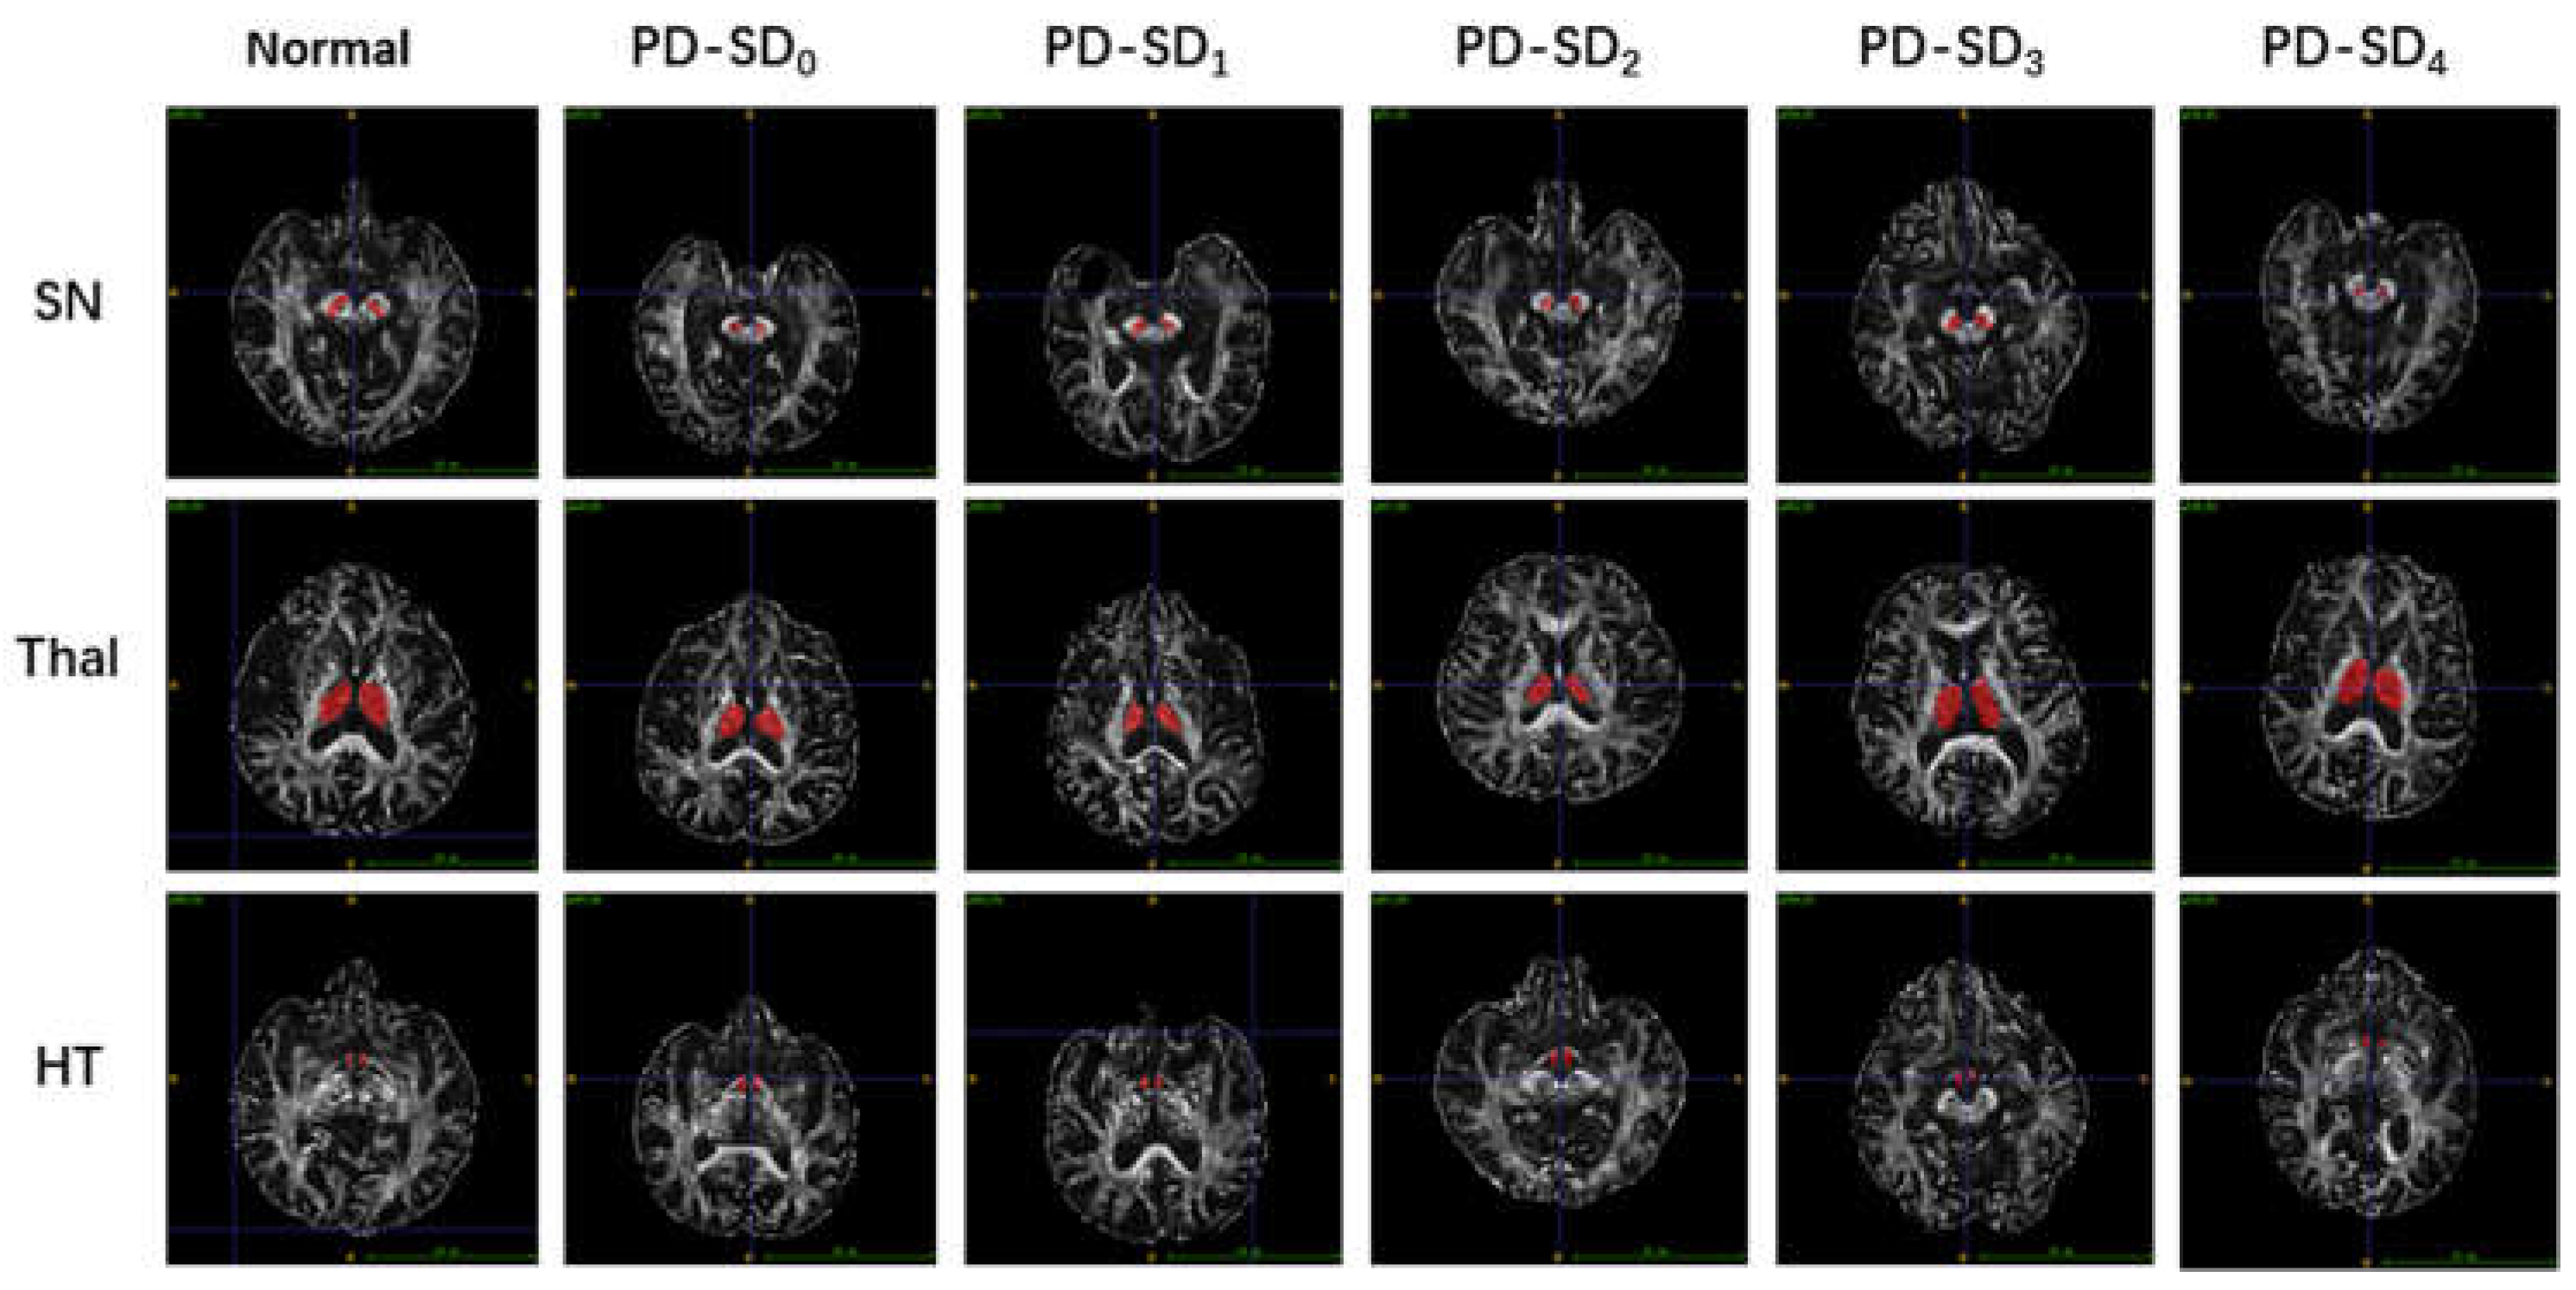

3.5. Imaging Characteristics of the Early PD Patients with Different Numbers of SD Types

3.7. Imaging Characteristics of the Early PD with Various SDs